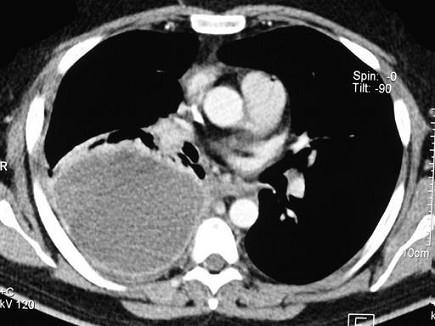

男,59岁,呼吸困难,胸痛,有发热,请结合CT图像选择最可能的诊断 ( )A、肺囊虫病B、肺癌C、肺脓肿D、大叶性肺炎E、脓胸

问题 男,59岁,呼吸困难,胸痛,有发热,请结合CT图像选择最可能的诊断 ( )

选项 A、肺囊虫病 B、肺癌 C、肺脓肿 D、大叶性肺炎 E、脓胸

答案 E